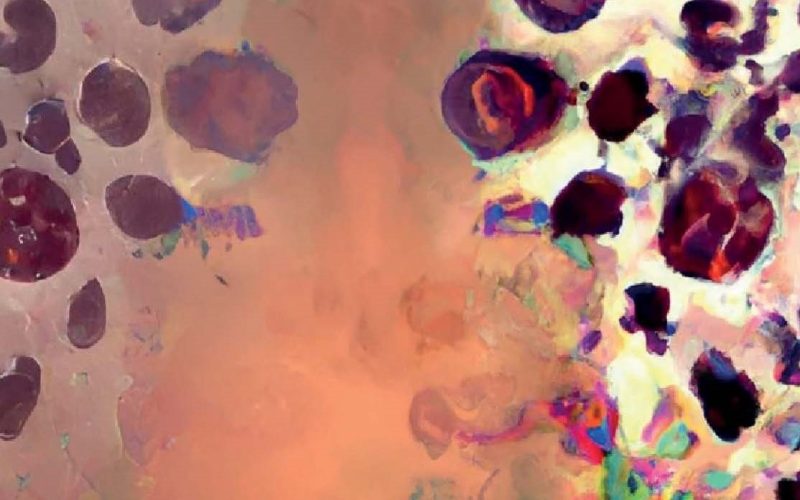

Neutrophils are widely acknowledged as the most abundant cell type of circulating leukocytes. With a prevalence of 2.5-7.5 million cells per liter blood (~60 percent of all leukocytes), neutrophils are unmistakably superior in numbers. They are essential defenders against infections, but not all neutrophils function alike. The PhD thesis by Suus Bongers, MD (Department of Trauma Surgery and Center for Translational Immunology, UMC Utrecht) reveals that distinct neutrophil subsets vary in both appearance and function and they appear in blood during different stages of inflammation, such as during the acute and sub-acute phases after severe trauma, endotoxemia, and COVID-19.

Critically ill patients often undergo extra inflammatory insults such as surgery, open wounds that can become infected and they are treated with invasive devices such as ventilators or drains. These factors contribute to a higher infection risk due to their invasive nature, but they also may cause additional ‘inflammatory hits’ and a disbalance of the immune response. Suus Bongers found that during the acute inflammatory phase (the first hours after traumatic injury), a subset called CD16dim (or banded) neutrophils predominates, showing a strong bacterial killing ability. In contrast, during the sub-acute phase (days to weeks after trauma), CD62Ldim (or hyper-segmented) neutrophils become more common. The latter have a lower capacity to kill bacteria, which suggests that while CD16dim neutrophils primarily serve an antibacterial role, CD62Ldim cells may have a more regulatory function. The downside is that the impaired bacterial killing capacity of the CD62Ldim cells may allow them to act as ‘Trojan horses’, harboring intracellular bacteria and potentially increasing infection risk in vulnerable patients.